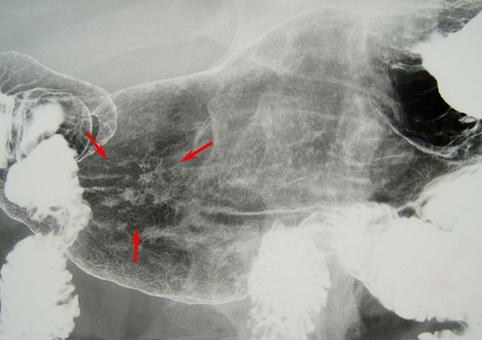

질환(병리주체)의 분류 악성 상피성종양/인환세포암

부위(장기별) 위(부위)/위각

검사방법 X-P

종양의 육안분류 0형(표재형)/IIc형(IIc+III)

종양의 최대경(밀리미터) 20~24

종양의 심달도 m